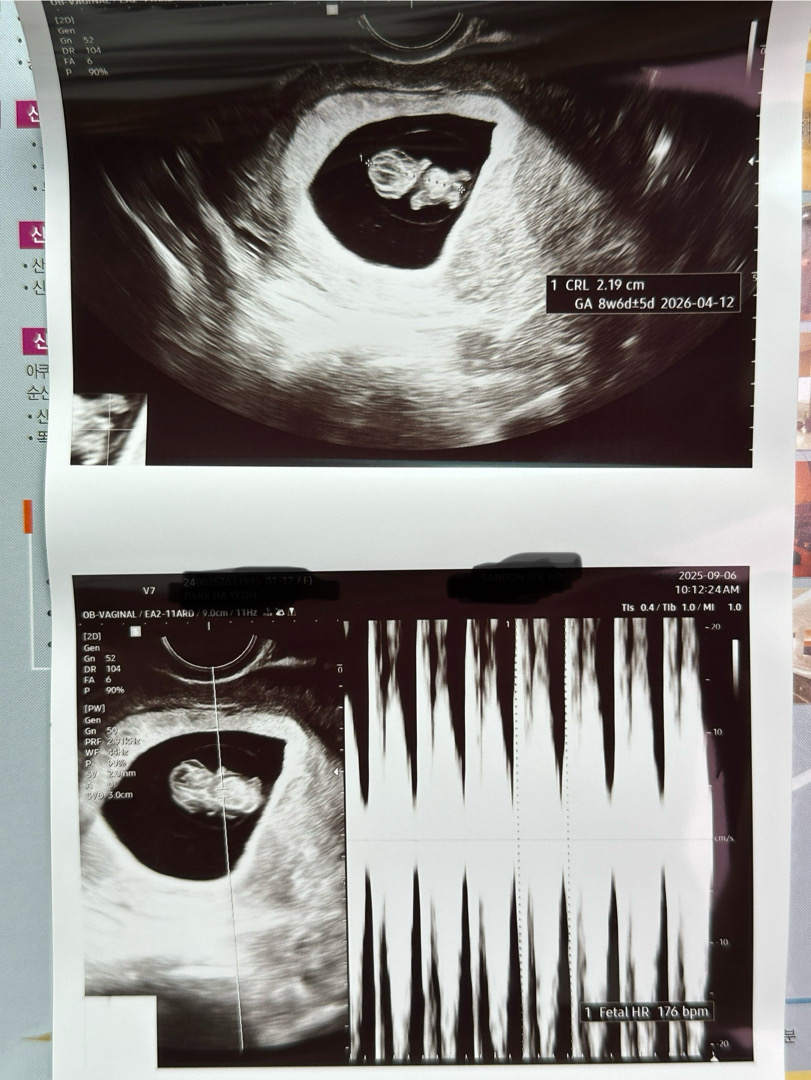

태아부종..

오능 8주6일차 초음파 봤는데 선생님이 아기가 부었다고.. 심장기형이나 기형아의심이 된다고 하시는데.. 이러다 또 나아질 수도 있다고는 하셨는데 혹시 아기가 부었다는 진단 받으신 분 계신가요..?2주후에 바로 니프티검사해보자고 하셔서 예약은 했는데 검사 결과 안좋으면 수술해야할 수도 있대서.. 괜찮아지는 경우가 있으셨을까요..? 초움파보면 다른 아기들 초음파 사진이랑은 조금 다룬 것 같아서... ㅠㅠ